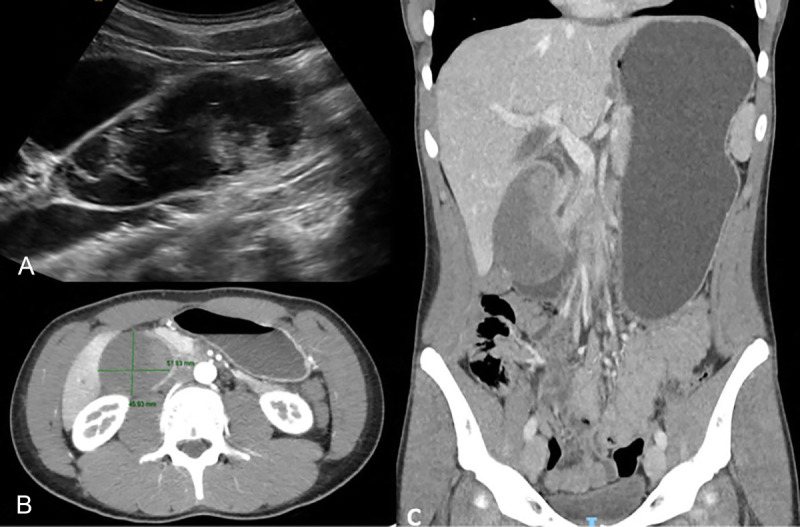

EUS-guided aspirate of a traumatic paraduodenal duodenal hematoma with gastric outlet obstruction (with videos).

eus引导下的外伤性十二指肠旁血肿伴胃出口梗阻的抽吸术(附录像)。